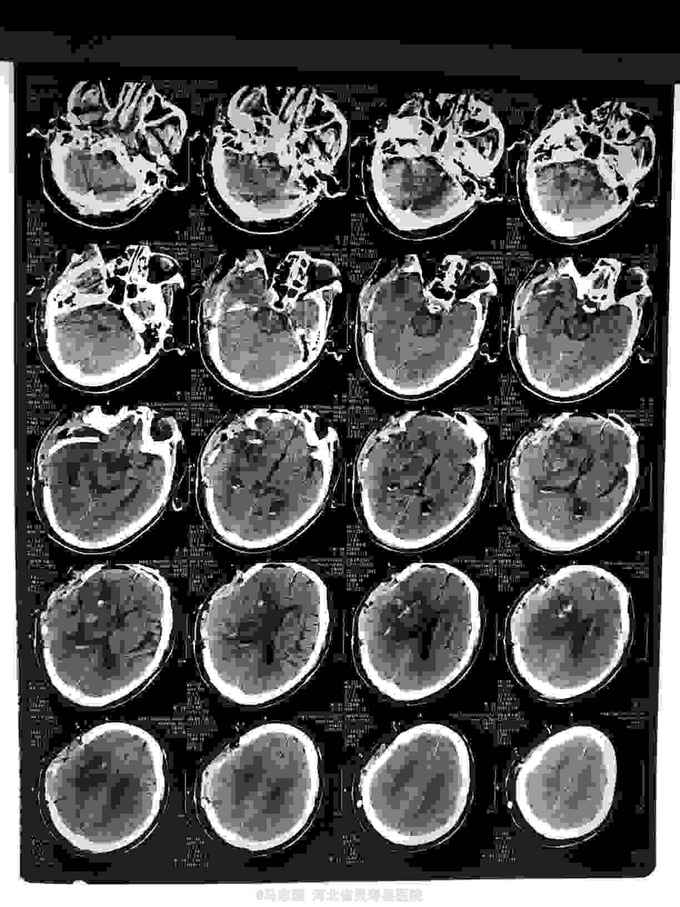

1.右侧基底节脑出血并脑疝形成2.高血压3级 极高危。急诊行血肿清除,去骨瓣减压术。术后给予降颅压,促醒保护脑神经等治疗。术后第二天复查CT如下

患者有高血压,未规律服用药物,且冬季天气寒冷,等可能导致血压升高,血管破裂,此类病人多有高血压病史,高血压未控制,如果口服抑制血小板药物阿司匹林等更易诱发出血。